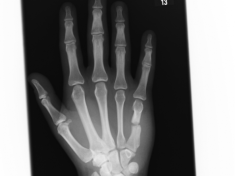

Röntgenbilder